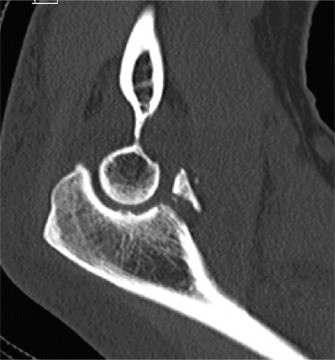

A 54-year-old male presented to the ED with left elbow pain after sustaining an injury in a low speed motor vehicle accident. He denied any other injuries. On examination, he had no open injuries and was neurovascularly intact. He had gross deformity about the elbow. His images are below (Figs. 2–89 to 2–92).

Figure 2–90 Pre- and post-reduction films showing complex elbow dislocation, coronoid fracture.

The correct answer is (C). Posteromedial complex elbow dislocation. This injury is proposed to result from axial load combined with posteromedial rotation, varus force, and elbow flexion. This is opposed to the more frequently seen posterolateral dislocation. There is a fracture of the coronoid, which is typical for this type of injury.

The correct answer is (A). Coronoid process fracture (see Fig. 2–93). The medial trochlea is thought to fracture the anteromedial facet of the coronoid allowing the elbow to dislocate. The lateral collateral ligament (LCL) ligamentous complex is also torn with this type of injury however the radial head often remains intact. This is in contrast to posterolateral elbow dislocations in which the radial head is the most commonly fractured bone, followed by the coronoid.